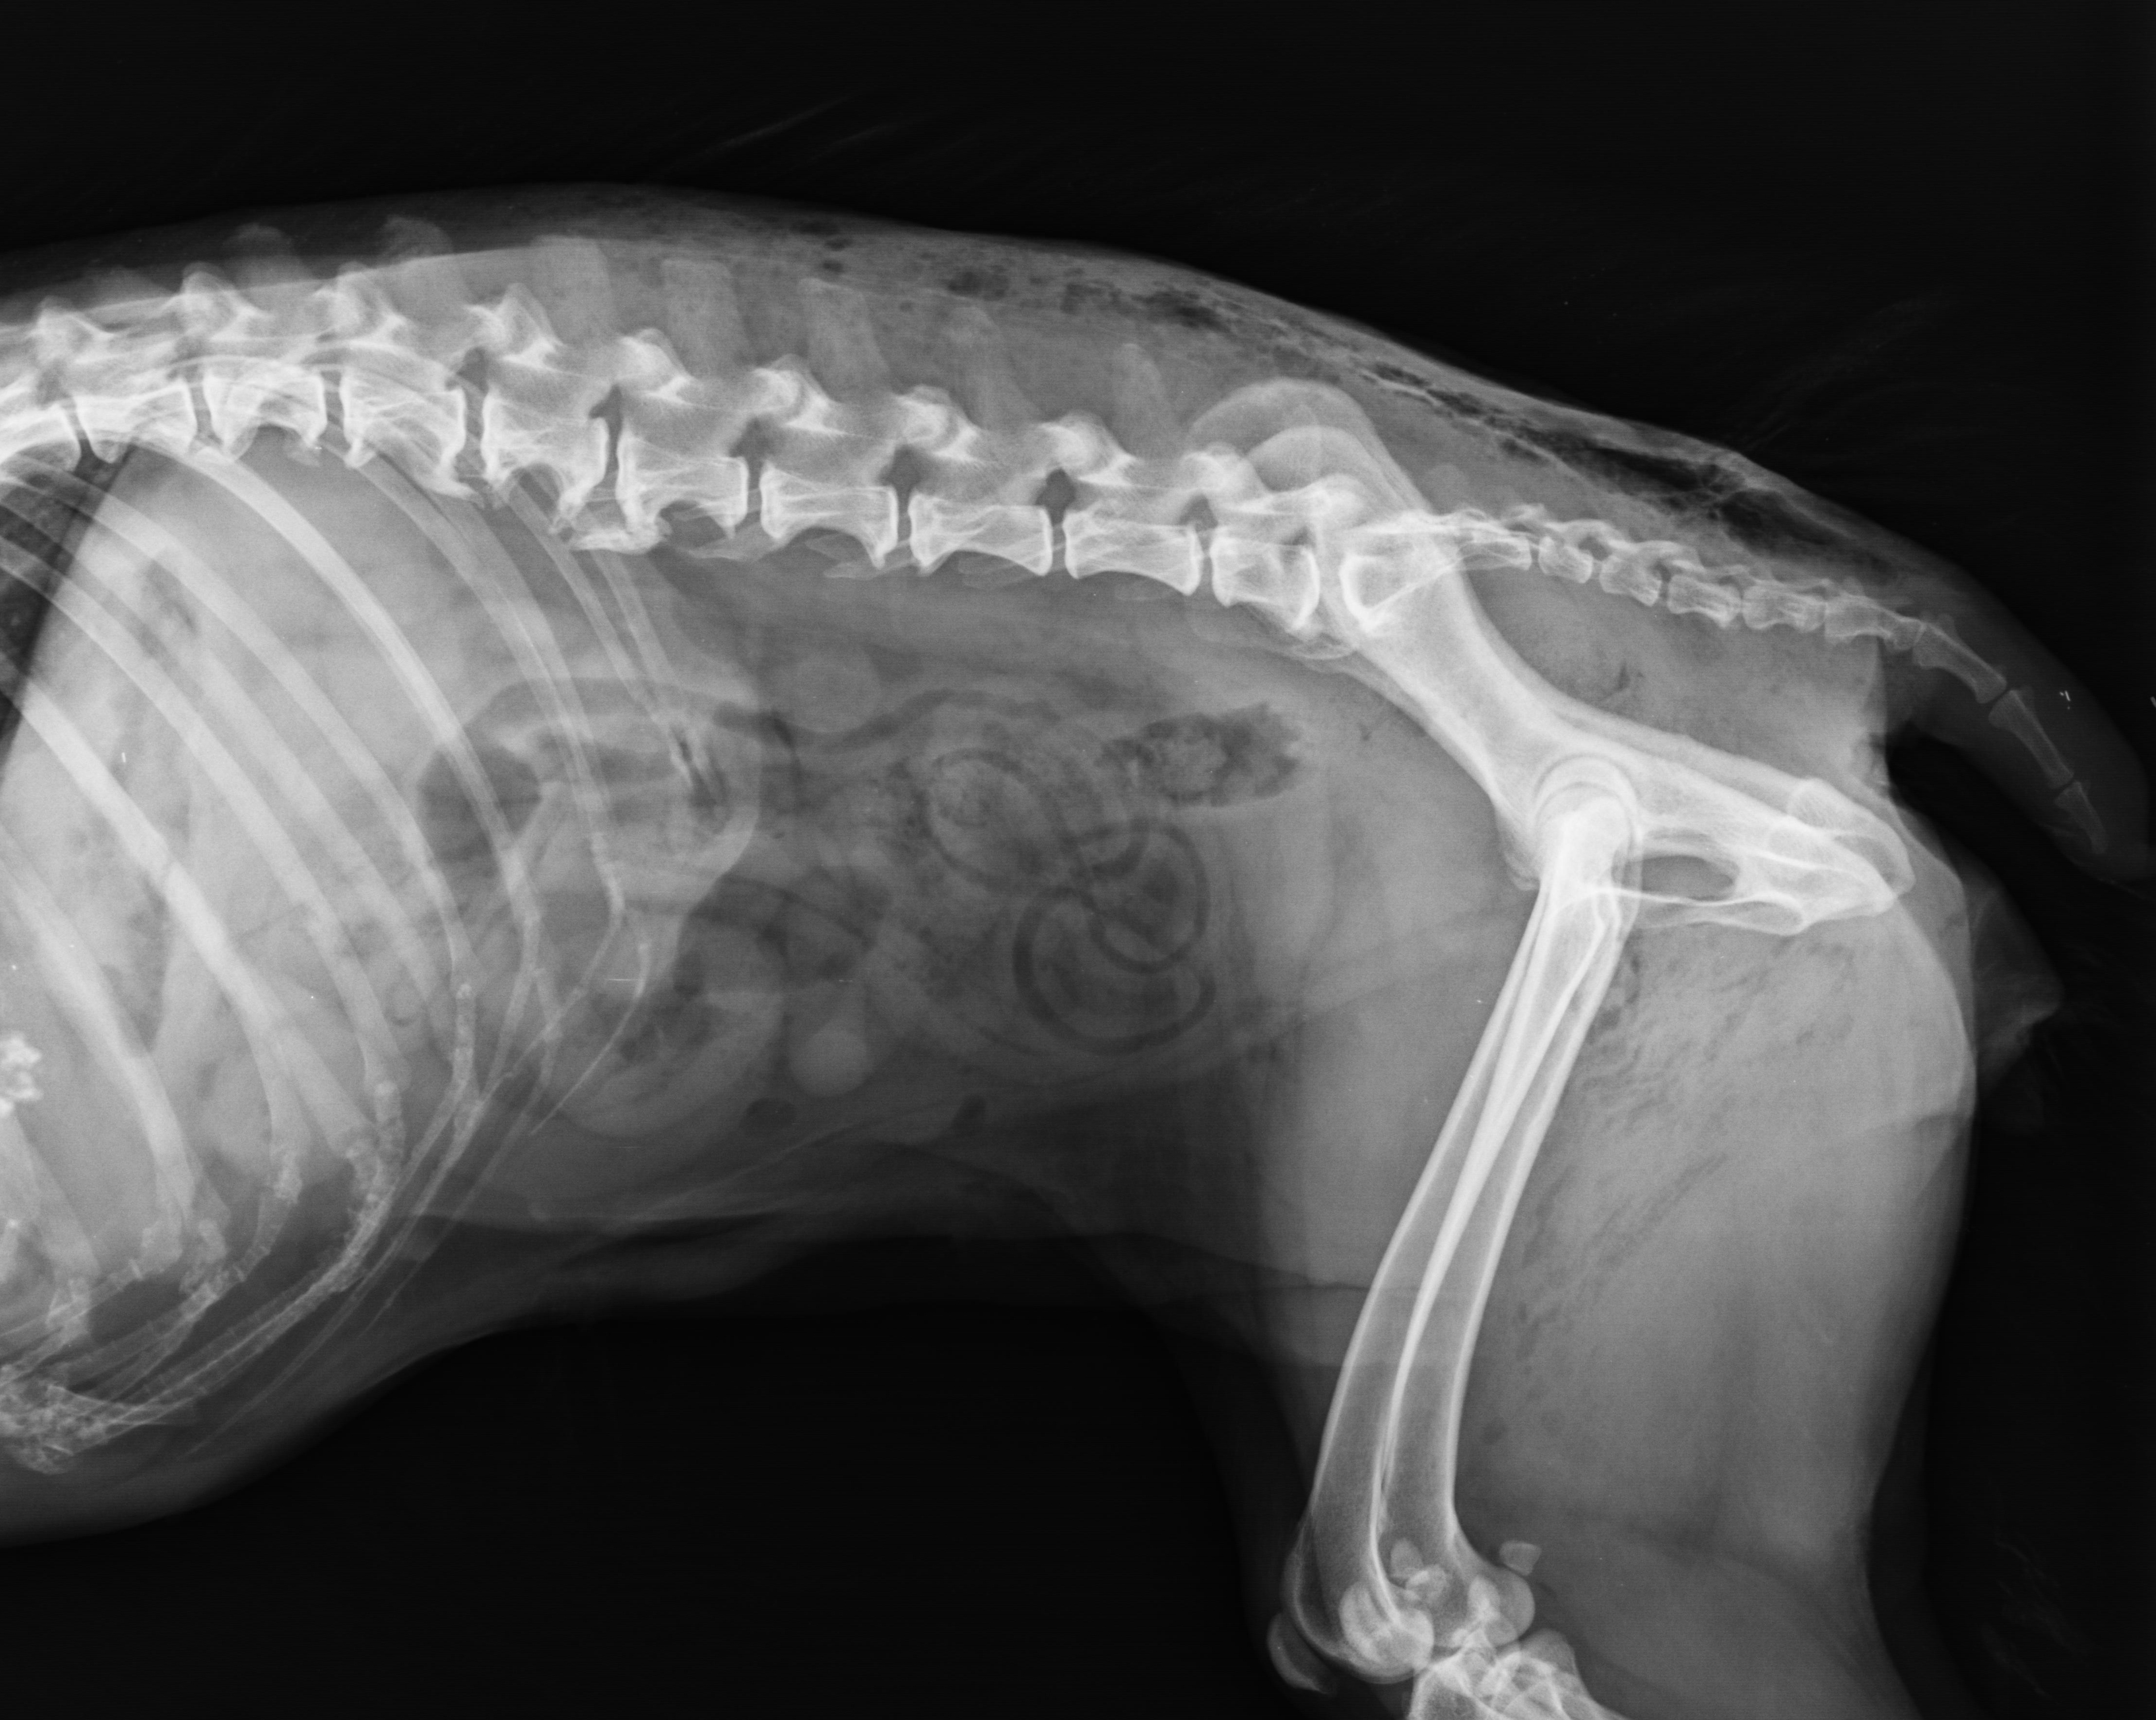

Osteoarthritis - Novel And Targeted Therapies That Can Alter The Course Of The Disease